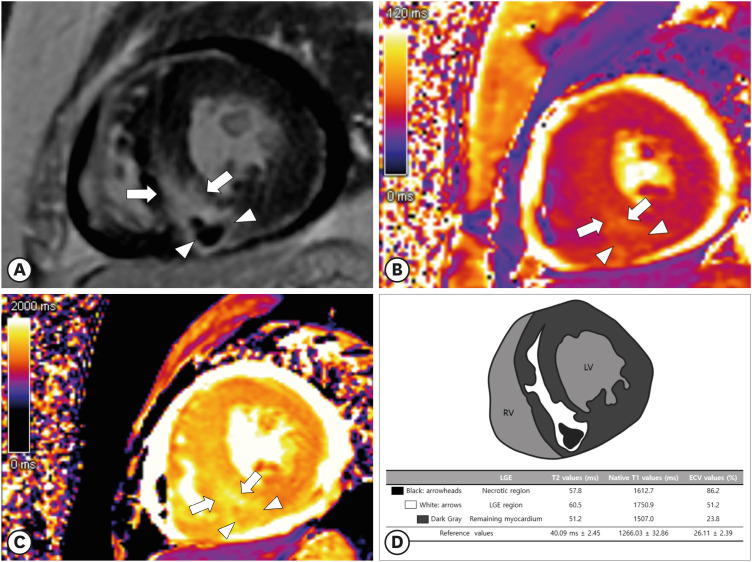

CMR参数定位有助于诊断急性淋巴细胞白血病复发时弥漫性心肌白血病浸润。

CMR Parametric Mapping Helps Diagnose Diffuse Myocardial Leukemic Infiltration in the Relapse of Acute Lymphoblastic Leukemia.